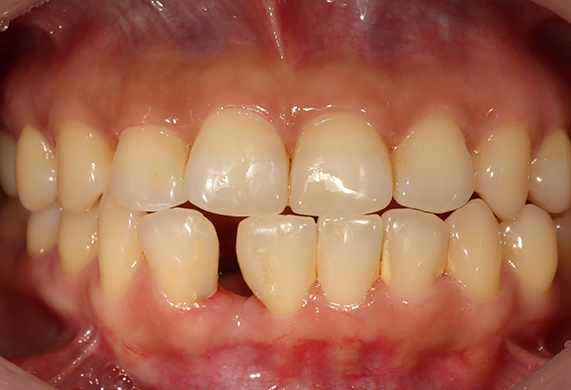

덧니 교정 CASE

-

연세바로치과는 치료법을 준수합니다. 로그인 하시면 Before를 보실 수 있습니다. LOGIN